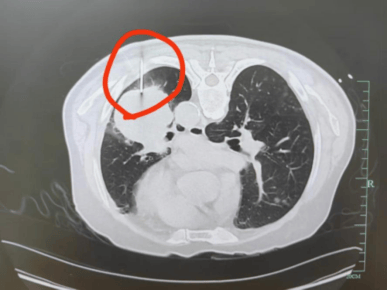

71岁的章爷爷咳嗽胸痛了半个月,儿女赶紧带他去浙大一院普胸外科检查,结果让全家揪紧了心:左肺有个4cm的肿瘤,考虑是中晚期,直接手术可能效果不佳,需要先行药物治疗控制肿瘤发展。但要制定治疗方案,必须先